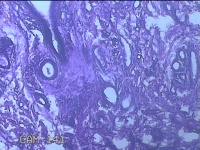

右下唇肿物

性别

女

年龄

12岁

临床诊断

唇囊肿

一般病史

右下唇部肿物一月余。

标本名称

大体所见

灰白粉红色肿物0.8x0.7x0.2cm一个,表面光滑。

图3